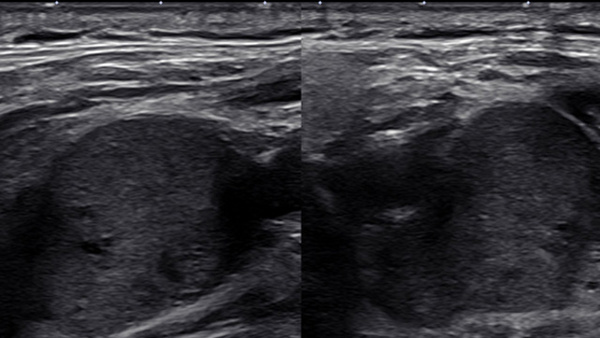

EVT For Ruptured PICA Aneurysm

AneurysmsStent assisted coiling

June 4, 2025